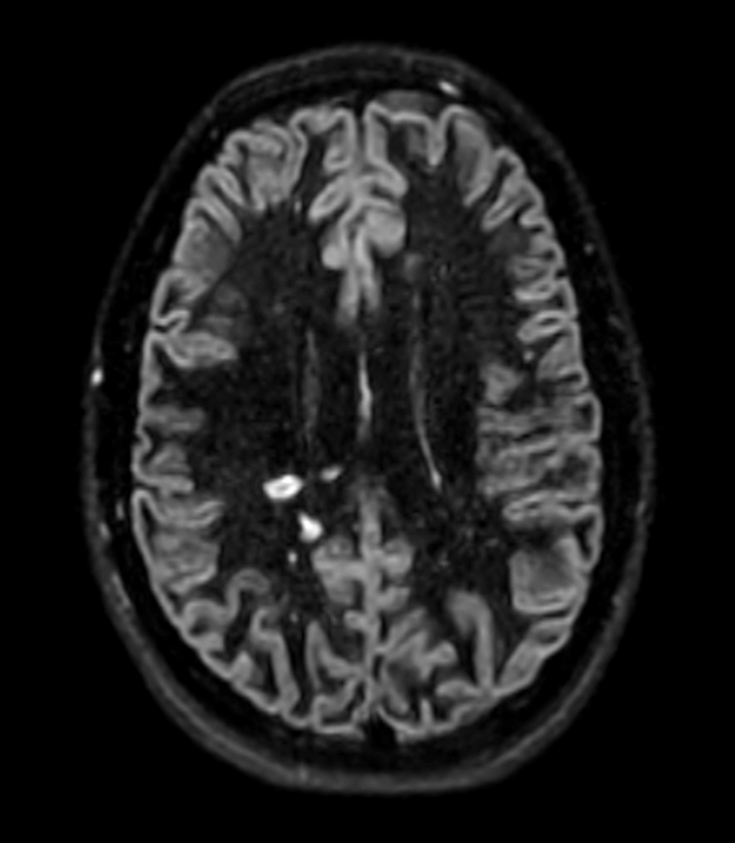

Patient with multiple brain lesions. ExamCard includes Compressed SENSE to shorten the exam time, 3D scans to acquire high resolution data in multiple directions in only one single scan and 4D-TRAK for dynamic contrast-enhanced MR Angiography enabling high spatial and temporal resolution simultaneously.

3D T2w FLAIR Compressed SENSE